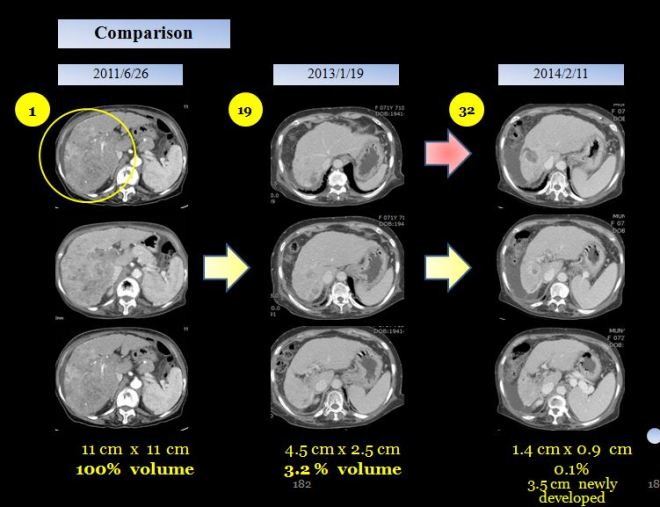

사진에서 보듯이 간은 위축이 되었지만 커다란 종양은 거의 없어져서 일부분만 남아 있다. 당시 의무기록을 보면,

“2011년 년 6월 9일과 2013년 1월 19일 CT 를 비교함. 간에 있던 최대 장경 11x11x10cm의 균일하지 않케 조영되는 암은 크게 감소하여서 2.5x 4.5로 줄어들었다. 우측간은 위축되어 있고, main과 우측의 portal vein의 종양에 의한 thrombosis 양이 줄어들었으나 남아 있고, portal vein (문맥)은 더욱 수축되어 있다. 간경화와 비장종대도 있다. 식도와 위장 부근의 비장 옆의 정맥류가 보이며 약간의 복수가 있다.”

18 개월만에 간의 종양이 거의 체적대비하여서 4% 정도로 줄어들었고 2014 년도 3월에 통합의학대회에서 본인이 강의하기 전에 환자에게 CT 를 찍어볼 것을 권유하였다. 이분은 광주분이라 거의 내원을 하지 않고 전화상담과 약물만 꾸준히 지어서 복용하였는데 만 3년이 넘은 2014년 봄에는 더욱더 종양이 줄어들었지만 부분적으로 재발소견을 보였다.